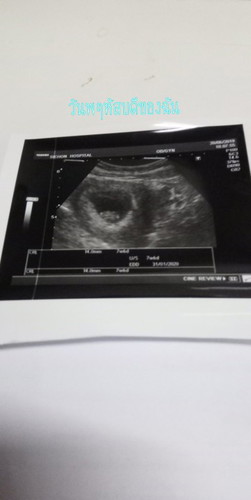

แต่งงานมา4ปี มีหลายคนถามเรา อยากมีลูกไม่ เราบอกรอเค้าให้มาเค้าไม่มา วันที่ตรวจเกือบช็อค? ในที่สุดเทอก้มา 4ปีที่รอ. ตอนนี้11สัปดาห์ 1วัน เป็นความรุ้สึกอธิบายไม่ถูก ดีใจจนน้ำตาไหล ตอนนี้รู้แค่ว่ารักทุกอย่างทำเพื่อเทอเด้กน้อย ❤❤

แม่ท้อง